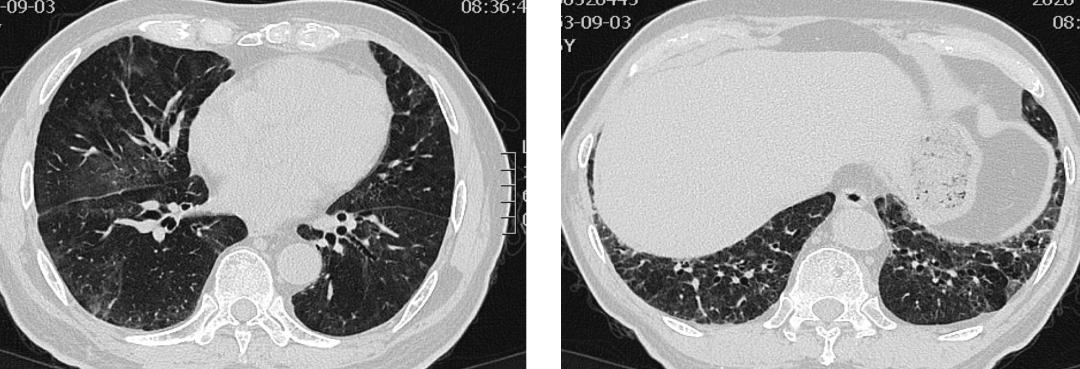

与highflow(FiO2 80%,吸气流速60L/min)立即予以丙种球蛋白10g*5天,甲强龙 120mg qd*3 天,后逐渐减至100mg*2天,80mg*2天,60mg*2天,40mg*10天后口服美卓乐32mg qd。甲强龙减量至60mg qd时加用他克莫司 1mg bid,经过2周治疗,患者氧合情况逐渐好转,可鼻导管(SaO2 95%–96%,2L/min)给氧;面部和眼睑浮肿好转,双手肿胀,和关节痛等症状明显好转,双手可以握拳。复查胸部CT双肺多发磨玻璃影较前吸收,复查肺功能弥散功能也较前好转。但双肺,尤其下肺纤维条索影改变明显。加用吡非尼酮200mg tid,并联合美卓乐32mg qd, 和他克莫司1mg bid维持治疗,每三周减1#美卓乐,2周后复查胸部CT显示双下肺渗出磨玻璃影,纤维条索影较前明显减轻。

(左:治疗前;右:大剂量皮质激素治疗7天后)